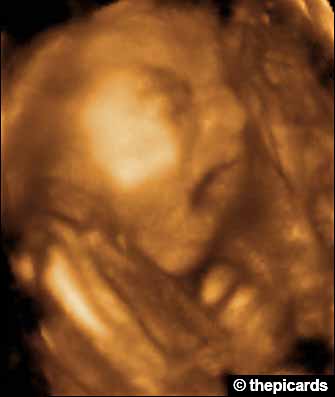

Fetus ultrasound

Fetus facial expression

Because their skin is so supple and not yet attached to the skull, fetuses can accomplish facial expressions that they will no longer be able to make as adults.

Even if no one can see, the fetus is continuously conveying its emotions through facial expressions and gestures.